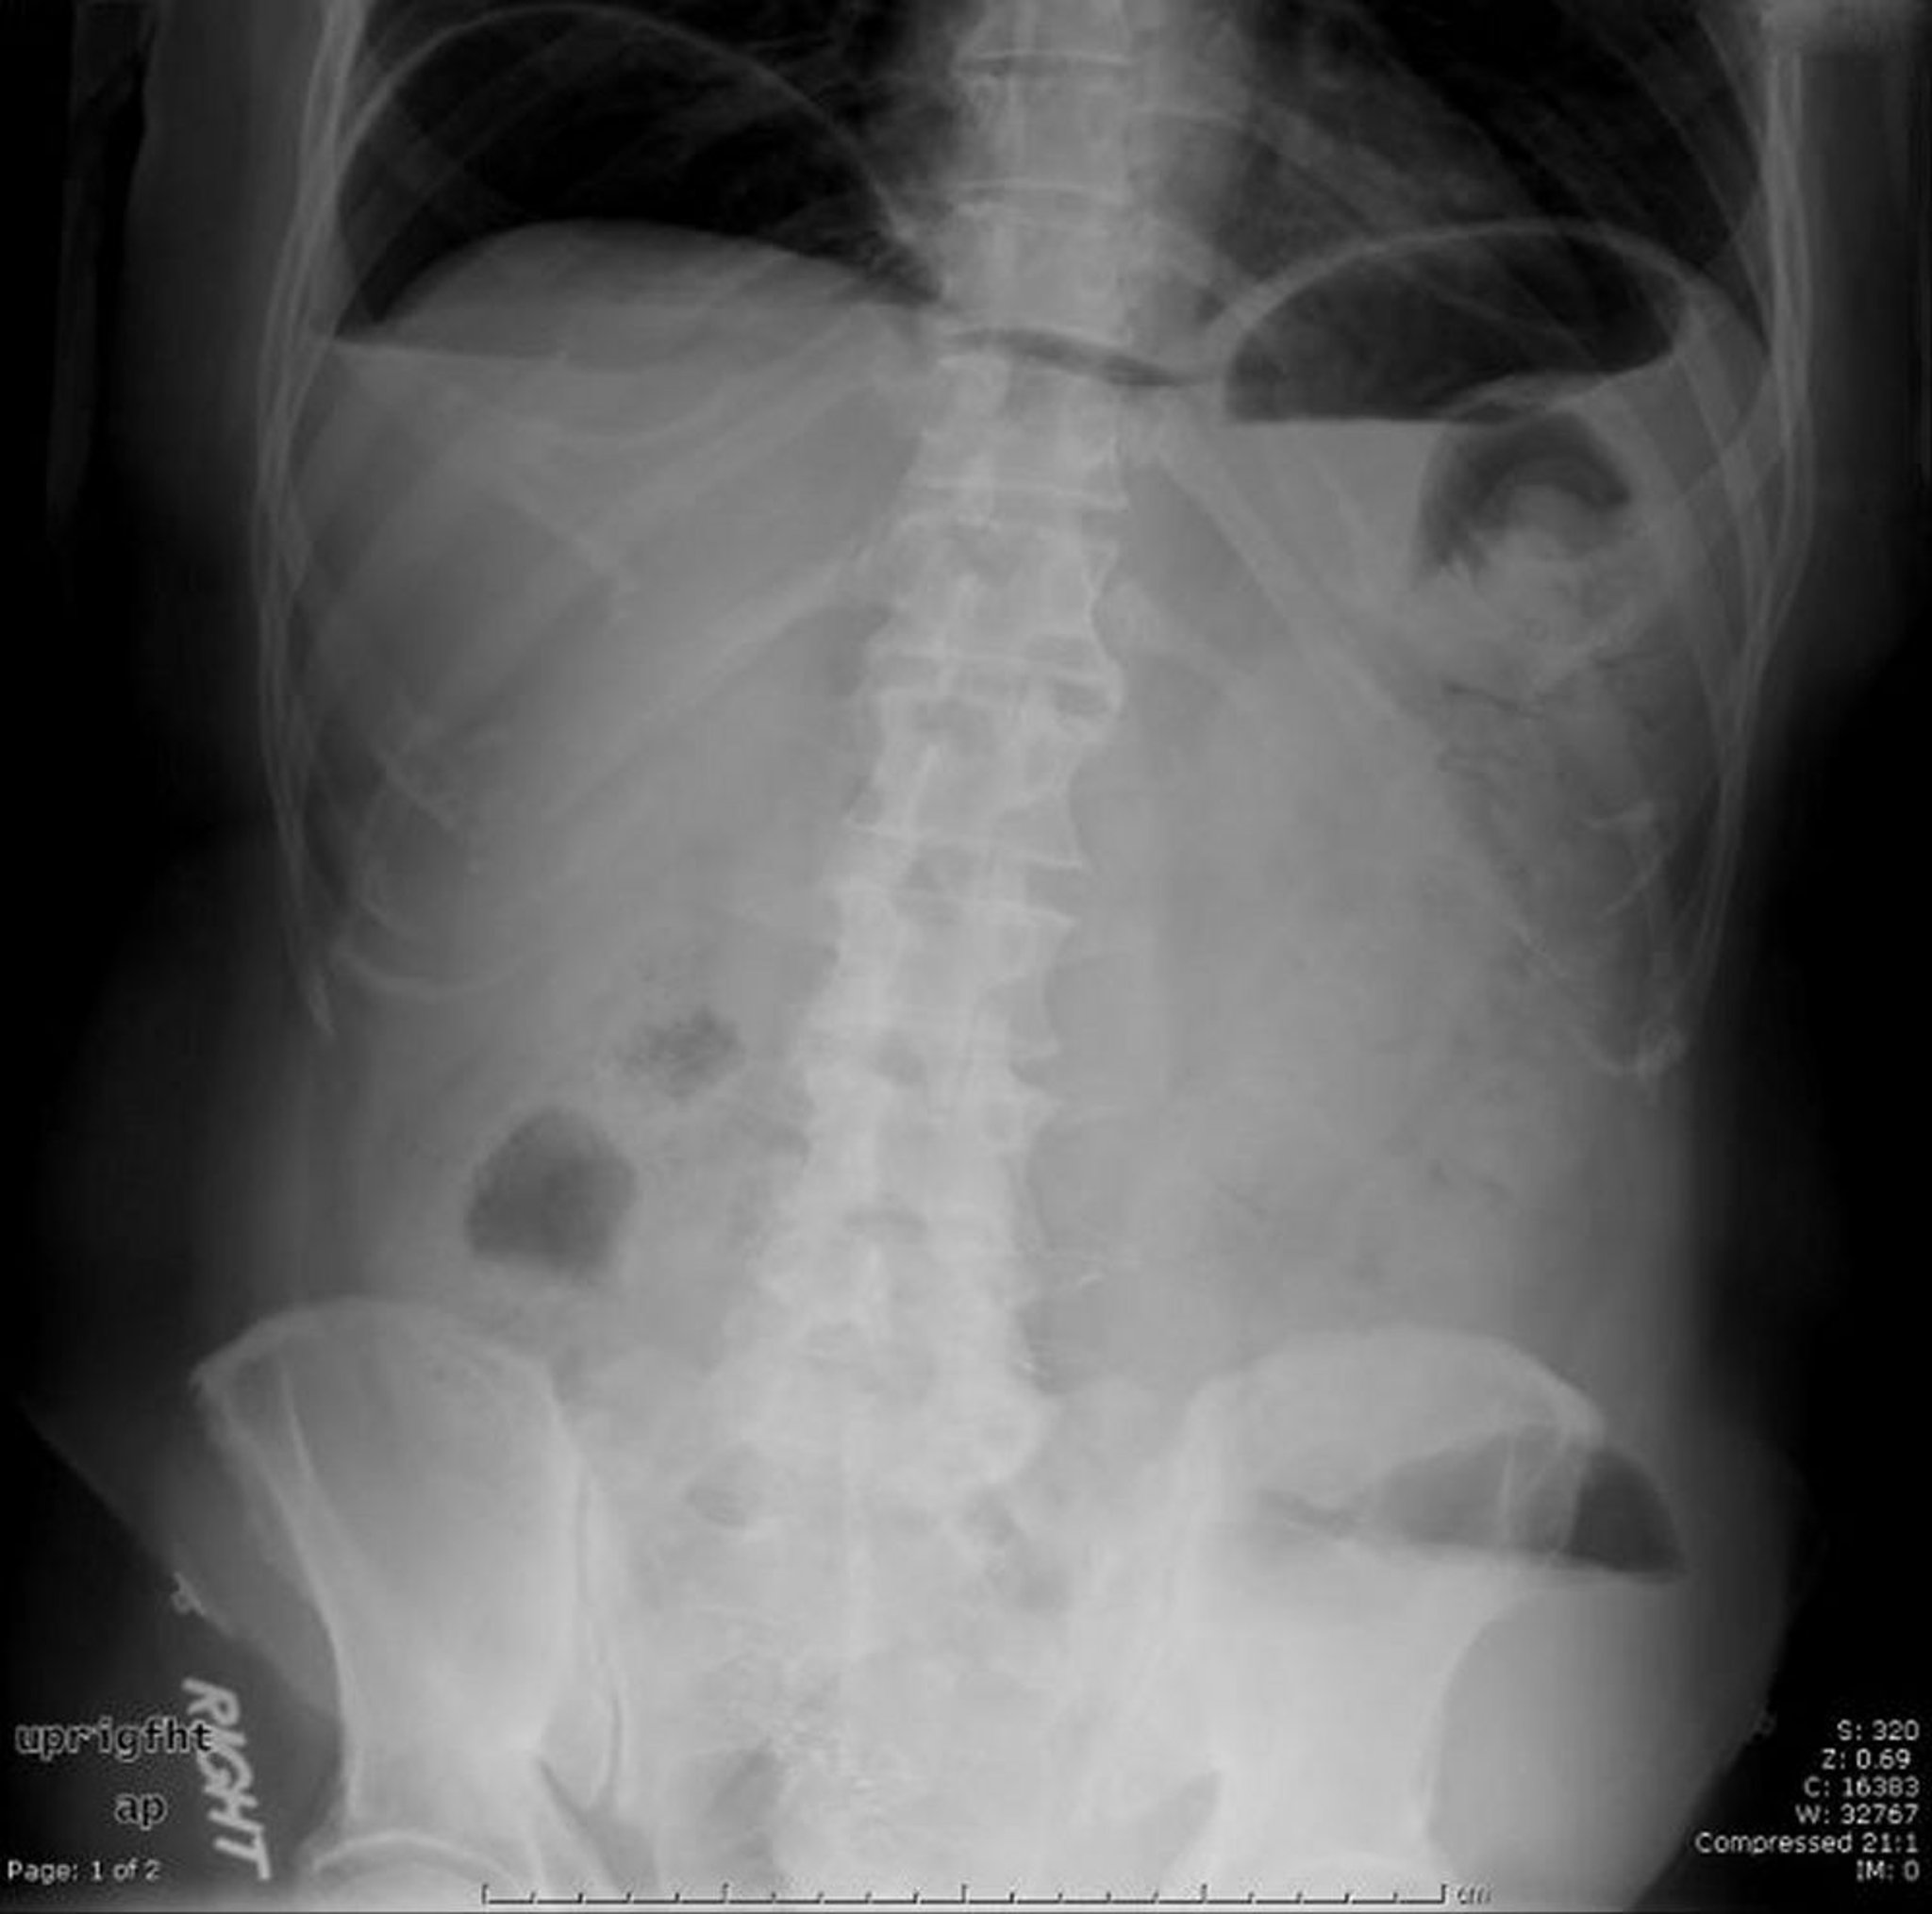

Aire libre

Esta radiografía abdominal muestra aire libre causado por una perforación.

Image provided by Parswa Ansari, MD.